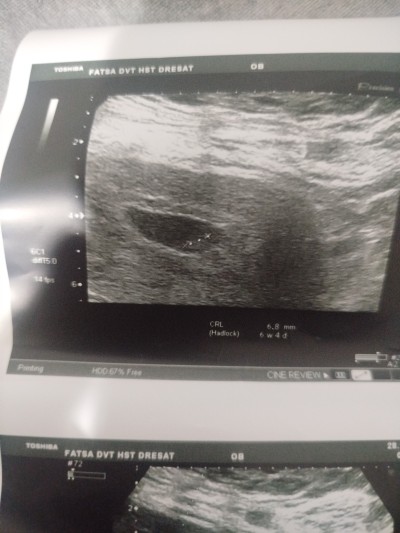

kese şeklıne gore cinsiyet tahmini ne ola bilir

Gebelik haftası 7+4

Sencede çok küçük degilmi kagita 6+4haftalik olduğu yazıyor kese şekli 19,20 haftalık olana kdr değişir artı doktorun göbeğe bastırmasıyla şekil alır şimdiden erken keseden beli olsa Dr derdi cnm.